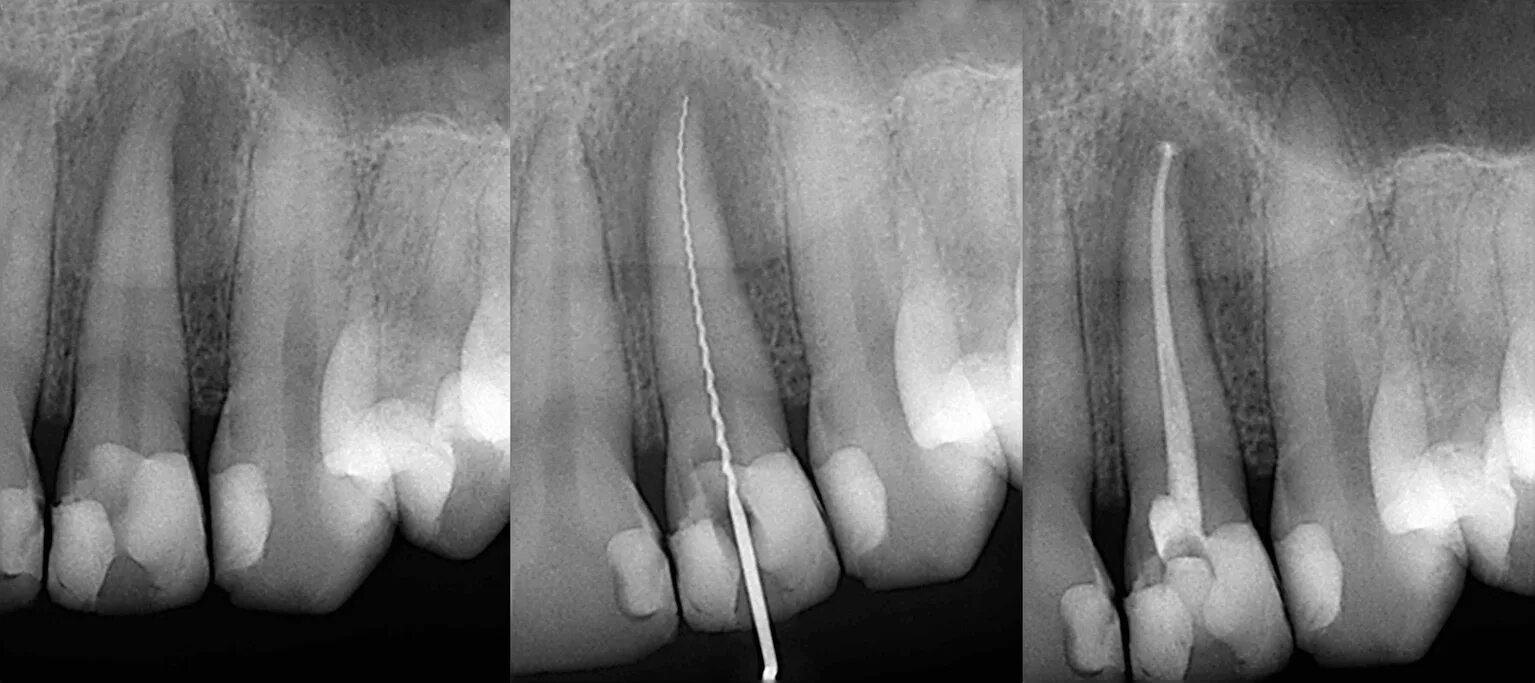

Лечение зубных каналов под микроскопом

Когда кариес добирается до пульпы («нерва»), развивается пульпит. Если инфекция идет дальше, в ткани вокруг корня — это периодонтит. Боль — лишь симптом. Реальная проблема — миллионы бактерий в сложной системе корневых каналов. Пропустить даже один из них, не найти дополнительный (атипичный) канал или не до конца очистить основной — значит обречь лечение на неудачу. Без увеличения это часто происходит незаметно для врача.

Представьте, что вам нужно прочистить и запломбировать три извилистых полых трубки толщиной с волос, спрятанных глубоко в челюсти. Без увеличения врач работает почти вслепую, на ощупь. Под микроскопом с увеличением в 20-30 раз эти «трубки» превращаются в хорошо освещенные тоннели, где виден каждый нюанс.

2. Под контролем микроскопа находим, измеряем длину (апекслокатором) и механически обрабатываем каждый канал.

4. Плотно и герметично пломбируем их гуттаперчей — материалом, ставшим золотым стандартом в эндодонтии.